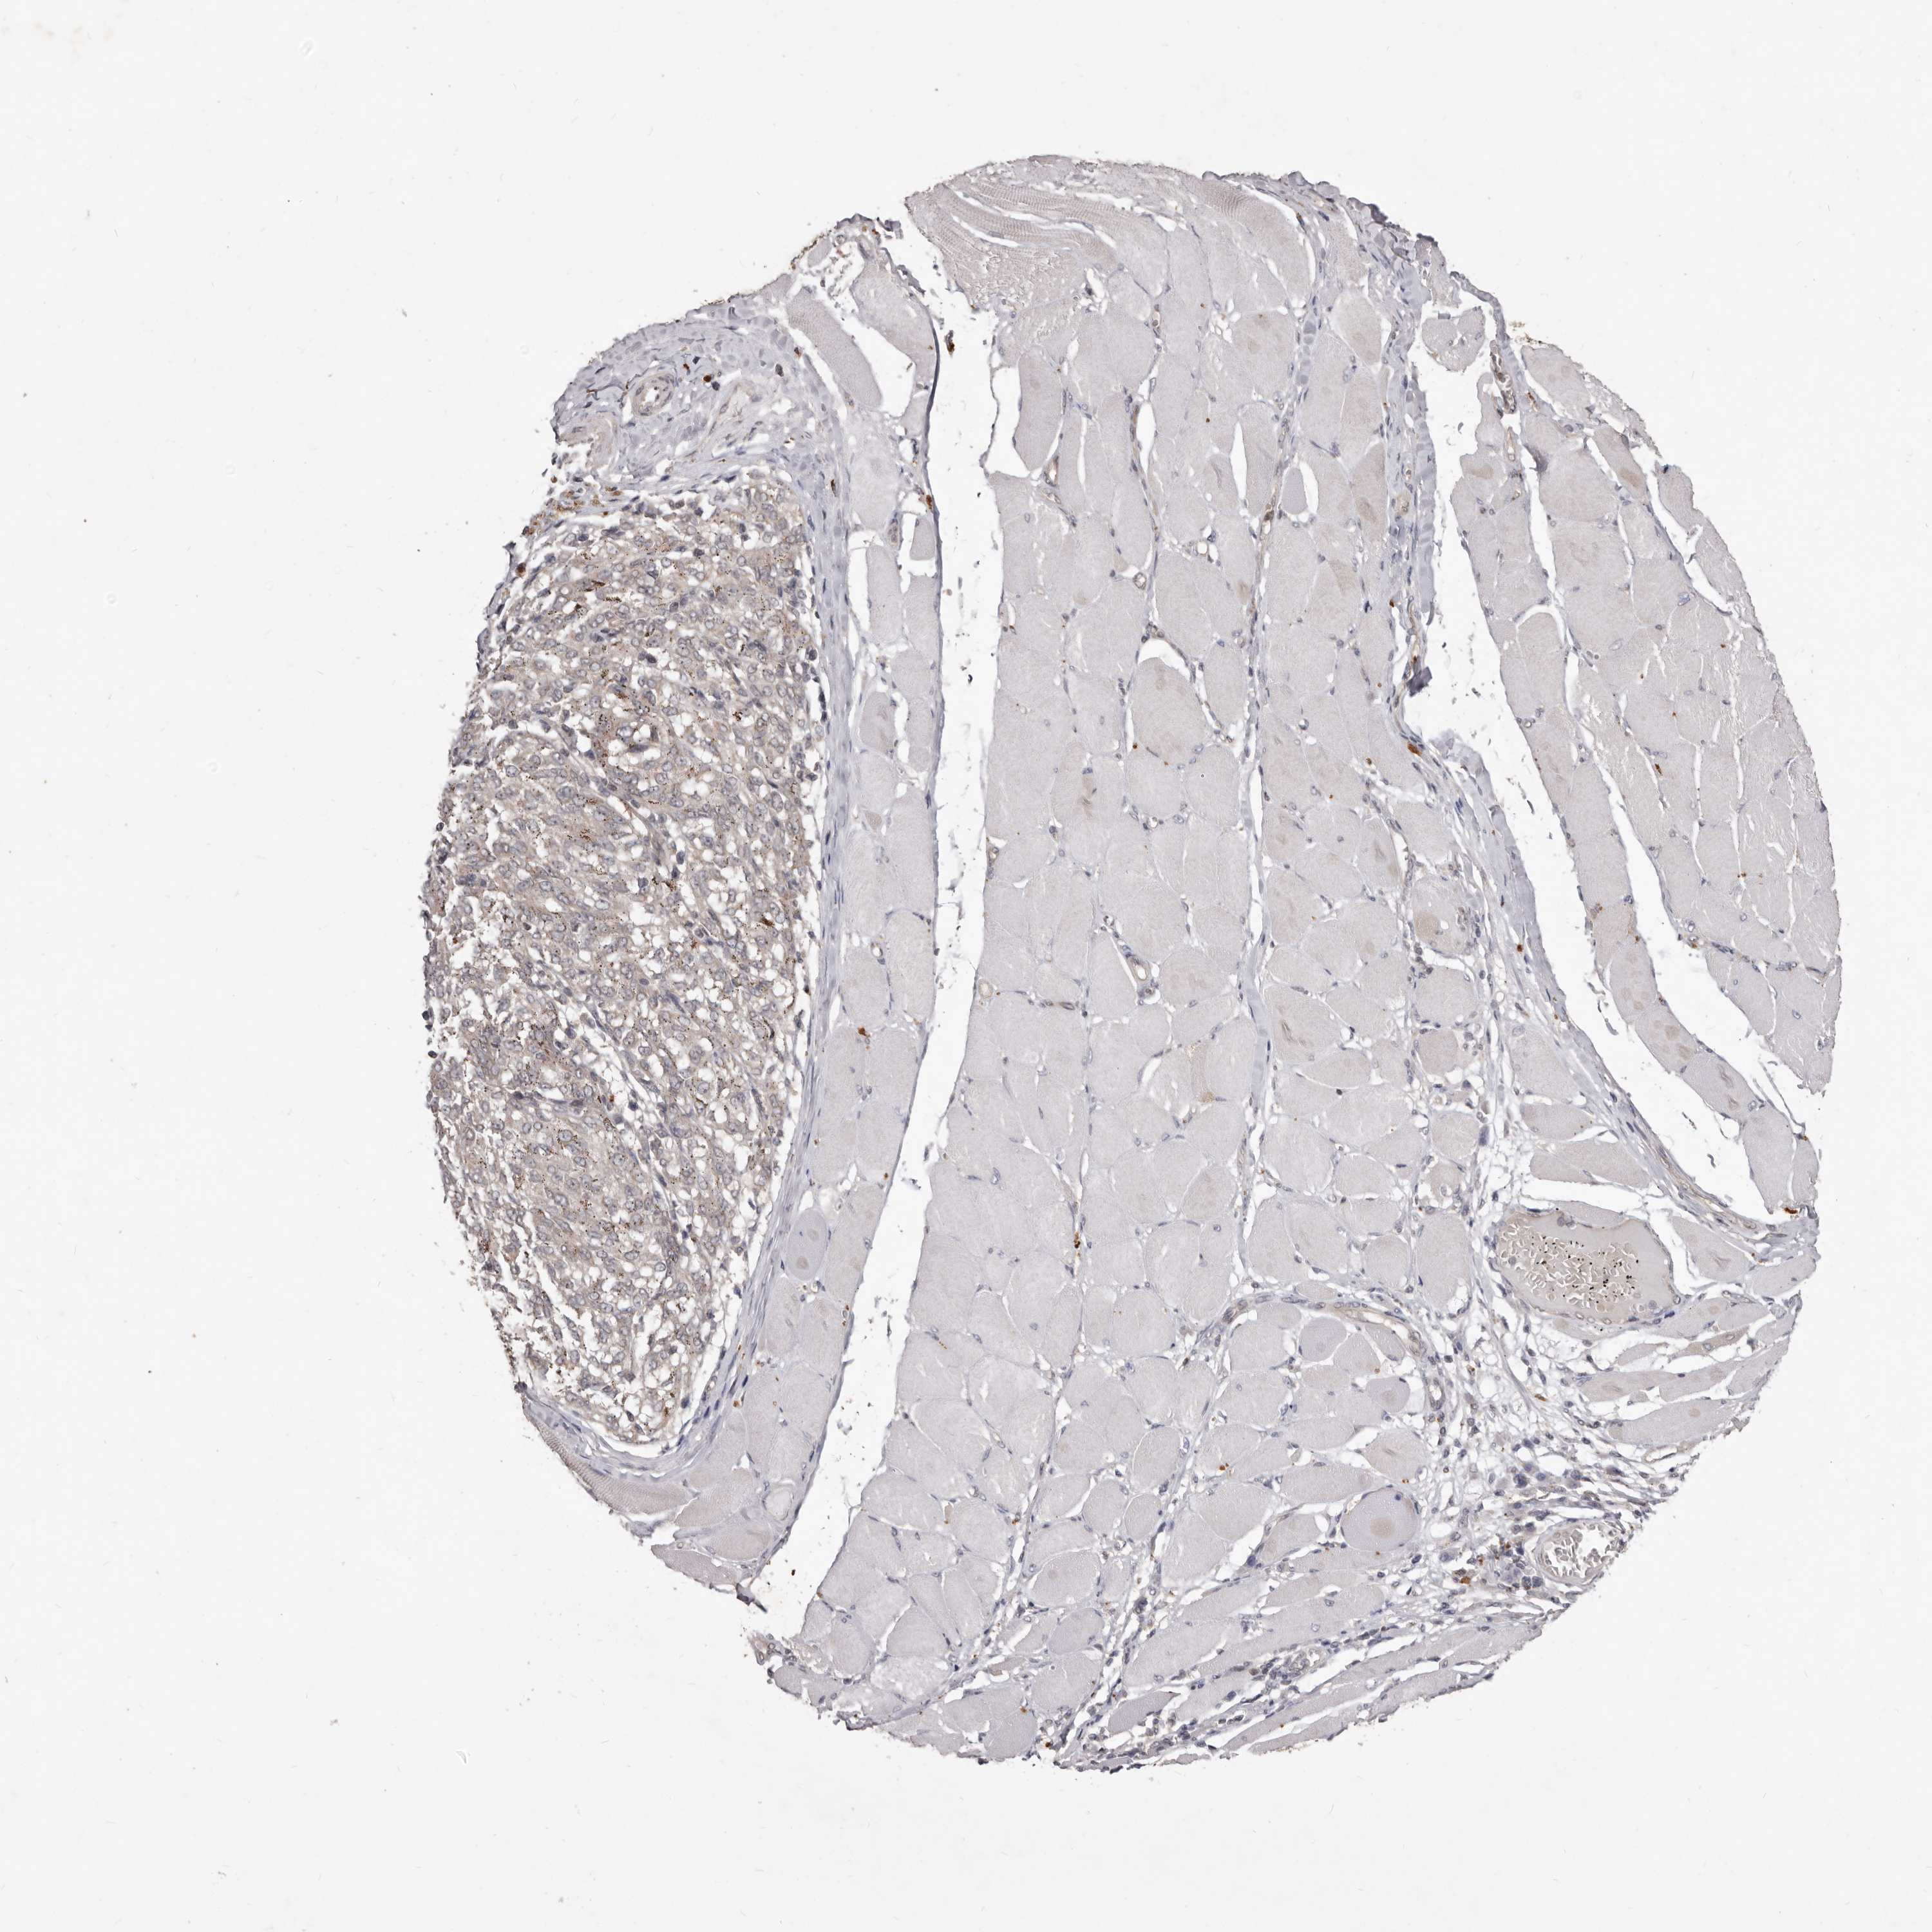

MELANOMA - Protein expressioni

A mouse-over function shows sample information and annotation data. Click on an image to view it in a full screen mode. Samples can be filtered based on level of antibody staining by selecting one or several of the following categories: high, medium, low and not detected. The assay and annotation is described here.

Note that samples used for immunohistochemistry by the Human Protein Atlas do not correspond to samples in the TCGA dataset.

Antibody stainingi

Antibody staining in the annotated cell types in the current human tissue is reported as not detected, low, medium, or high, based on conventional immunohistochemistry profiling in selected tissues. This score is based on the combination of the staining intensity and fraction of stained cells.

Each image is clickable and will lead to virtual microscopy that enables deeper exploration of all samples and also displays staining intensity scores, fraction scores and subcellular localization as well as patient and tissue information for each sample.

HPA022434

HPA022953

HPA022959

HPA028758

CAB007783

Staining

High

Medium

Low

Not detected

Intensity

Strong

Moderate

Weak

Negative

Quantity

>75%

75%-25%

<25%

None

Location

Nuclear

Cytoplasmic/membranous

Cytoplasmic/membranous,nuclear

Malignant melanoma, NOS

Malignant melanoma, Metastatic site